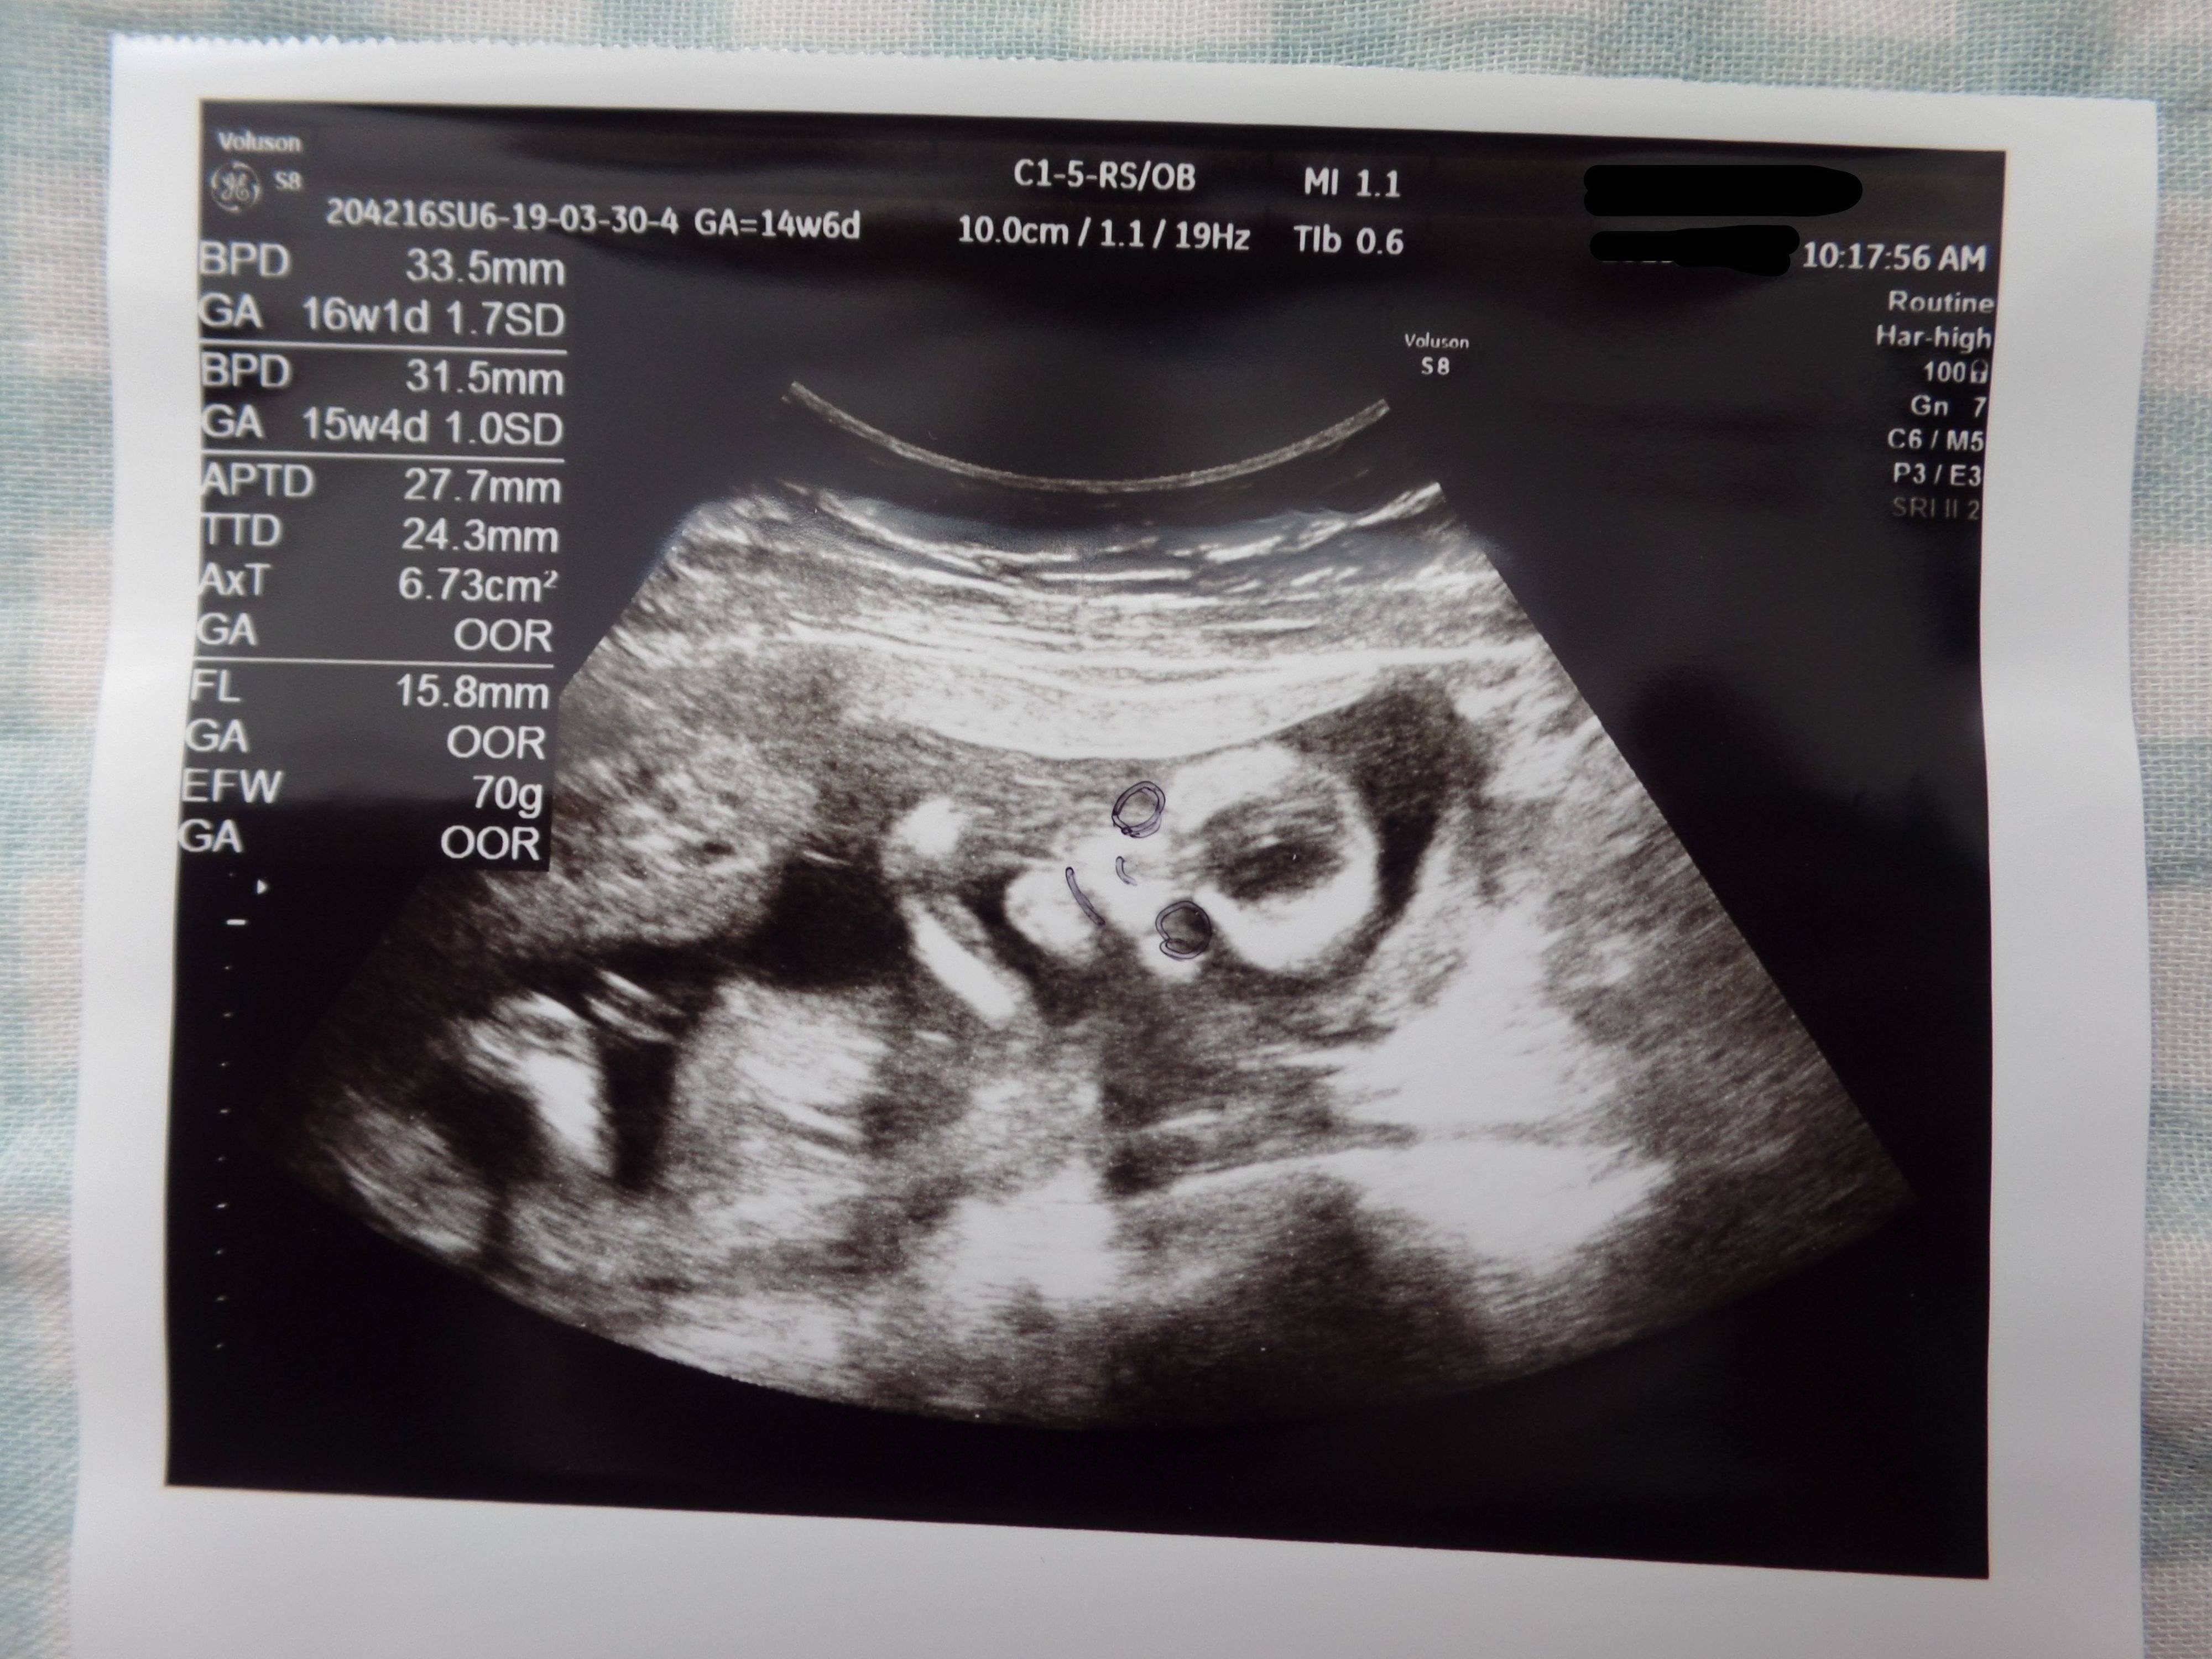

3. 多嚢胞性卵巣症候群(PCOS)から不妊治療を経て高齢出産! エコー写真で喜びを振り返る